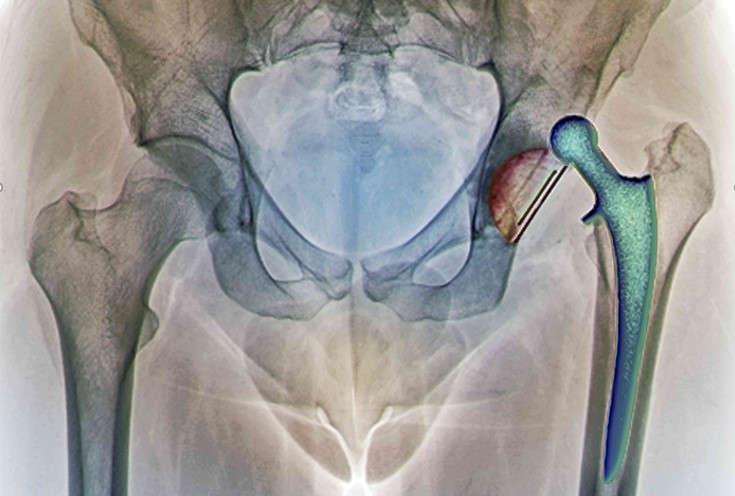

Почнемо з невеликого клінічного прикладу ревізійного ендопротезування

У 2008 році пацієнту було виконано операцію – тотальне ендопротезування лівого кульшового суглоба. Через 12 років пацієнт звернувся зі скаргами на біль у ділянці прооперованого суглоба. На контольному знімку виявлено явні зміни в області вертлужного компонента ендопротезу. Попередній діагноз: остеоліз, металоз (можлива інфекція), знос компонентів у місці тертя. Вертлужний компонент протезу встановлений вище анатомічного місця розташування.

• З додаткових обстежень були призначені: КТ, ангіографія, пункція кульшового суглоба для виявлення можливої інфекції

• Додаткове дослідження не виявило інфекції, а також показало, що ніжка ендопротезу залишилася стабільною і функціональною

• Було прийнято рішення використовувати для заміни вертлюжного компонента індивідуальний 3D імплант кульшової западини

Результат – виконано ревізійне ендопротезування лівого кульшового суглоба – встановлено індивідуальний вертлужний компонент